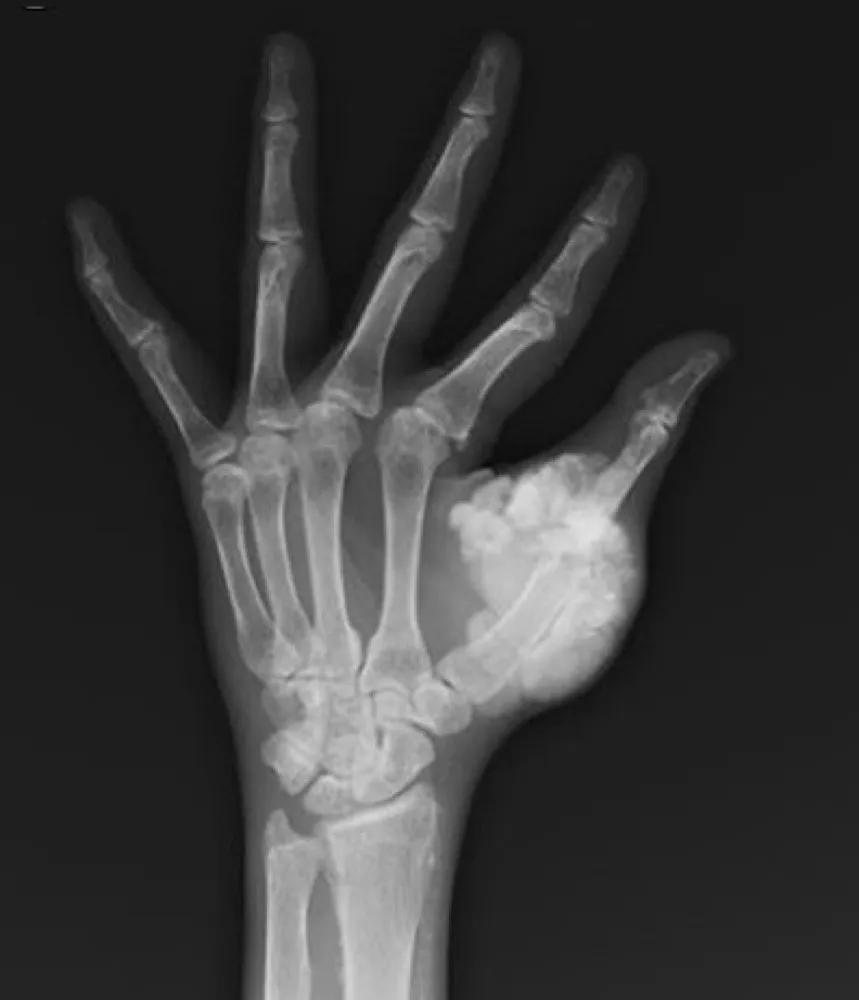

Eu sempre tento lembrar desta figura clássica: